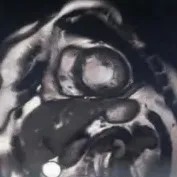

入院后监测患者病情变化,患者住院后经上述对症治疗,呼吸困难及胸闷症状逐渐好转。结合患者病史、既往及本次超声心动图改变,高度怀疑左室心肌致密化不全LVNC。为进一步明确诊断及评估心脏结构改变,完善了心脏磁共振检查。结果显示左室侧壁及心尖部过度肌小梁化,非致密心肌厚度大于致密心肌厚度的2~3倍,左心室整体收缩功能减弱,并见心尖部心内膜下钆延迟增强(图1)。

图1. 心脏磁共振